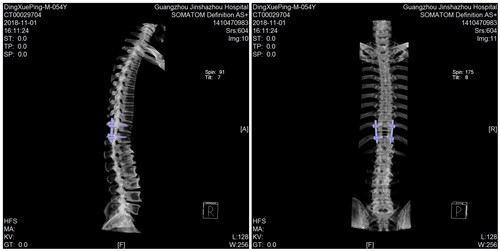

胸椎内固定术后CT

经过详细地询问病史和全面的体格检查,CT提示黄韧带骨化,相应胸椎管狭窄。丁叔就是由于胸椎黄韧带骨化,压迫胸髓引起左下肢痉挛性瘫痪,左下肢僵硬、活动不便、偏瘫步态,严重影响日常生活。

骨科中心郑主任精心为丁叔制定了详细的手术方案,做好了充分的术前准备,降低了手术风险,使得丁叔的手术顺利完成,术后左下肢肌张力明显下降,肢体活动灵活、行走步态明显改善,临床治疗效果佳,经过几天的康复锻炼和功能训练,现在丁叔已康复出院、平安归家。